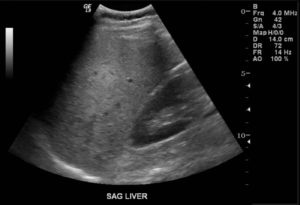

Диагноз в случае стеатоза ставится на основе инструментальных методов исследования — УЗИ печени, биохимического анализа крови. На УЗИ печень имеет «пестрый» вид за счет неравномерной структуры заполненных жирами гепатоцитов, а в анализах крови повышаются печеночные ферменты (АСАТ, АЛАТ), а также липиды крови, что отражает тесную связь между нарушением липидного обмена и стеатозом.

УЗИ печени позволяет выявить морфологические и структурные изменения органа, такие как:

- Гиперэхогенность – уплотнение тканей.

- Гепатомегалию – увеличение размеров печени.

- Жировую инфильтрацию – скопление веществ, которые в норме отсутствуют.

- Неоднородность плотности органа.

Признаки жирового гепатоза на УЗИ

Гепатоз на УЗИ и КТ выявляется только после начала изменения структуры печени. Направления на эти исследования выписывают, когда печень уже увеличилась в объеме, и это удалось обнаружить при пальпации.

При УЗИ могут быть выявлены следующие эхопризнаки гепатоза:

- уплотнение тканей печени

- увеличение размеров органа и его выход за края подреберной области

- жировое перерождение тканей печени

- неоднородность распространения поврежденных участков по органу.

УЗИ-признаки жирового гепатоза печени

Выделяют диффузную, локальную, очаговую и периферическую формы жировой инфильтрации, которые отличаются лишь распространением поражения. При диффузной форме размеры печени умеренно увеличиваются, но форма при этом не меняется.

Ультразвуковое исследование показывает снижение звукопроводимости органа, которое проявляется неотчетливой визуализацией глубоких отделов печени и диафрагмы и ухудшением визуализации мелких ветвей венозного рисунка.

- ультразвуковое сканирование печени и смежных органов брюшной полости. На УЗИ жировой гепатоз печени можно обнаружить даже на ранних стадиях, когда поражен только один участок или сегмент. Высокоэффективно УЗИ с эластографией, при которой благодаря цветному окрашиванию органа определяется изменение его плотности;